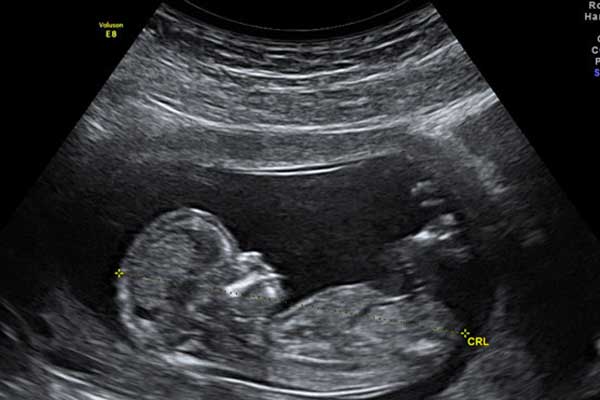

نینی سایت: دکترحسن بیات_دکترای علوم آزمایشگاهی: در سالهای اخیر، انجام آزمایشهایی با عنوان «آزمایش سلامت جنین» برای خانمهای باردار رواج یافته است. این آزمایشها که اصطلاح مناسبترشان غربالگریهای پیشزایمانی است برای بررسی میزان احتمال ابتلای جنین به اختلالات خاص مانند سندرم داون انجام میشود. همچنین میتوان با این آزمایشها احتمال ابتلای مادر به فشارخون حاملگی و مسمومیت بارداری(پرهاکلامسی) را نیز تعیین کرد. تا چندسال پیش این بررسیها با انجام آزمایشهای بیوشیمیایی در سه ماهه اول و دوم بارداری انجام میشد اما در چند سال اخیر میتوان در سهماهه اول آزمایش ژنتیک هم انجام داد که نتیجه آن به مراتب بر آزمایش بیوشیمیایی برتری دارد و البته قیمت آن حدود 15 برابر گرانتر از آزمایش بیوشیمیایی است. آنچه که در رابطه با این آزمایشها باید در نظر داشته باشیم این است که با وجود نام سلامت جنین به هیچ عنوان نمیتوانند با قطعیت درباره سلامت یا بیماری جنین نظر بدهند بلکه میزان احتمال ابتلا به بیماریهای موردنظر یا به اصطلاح میزان خطر را تعیین میکنند و سپس پزشک بر اساس آن احتمالات تعیین شده تصمیم میگیرد که گام بعدی چه باید باشد. اگر احتمال ابتلا به هر یک از اختلالات مورد نظر بالا باشد، بسته به میزان خطر بررسیهای بیشتری شامل سونوگرافی، مشاوره ژنتیک، نمونهگیری ازپرزهای جفت یا کیسهآب (کیسه آمنیوتیک) انجام میشود.